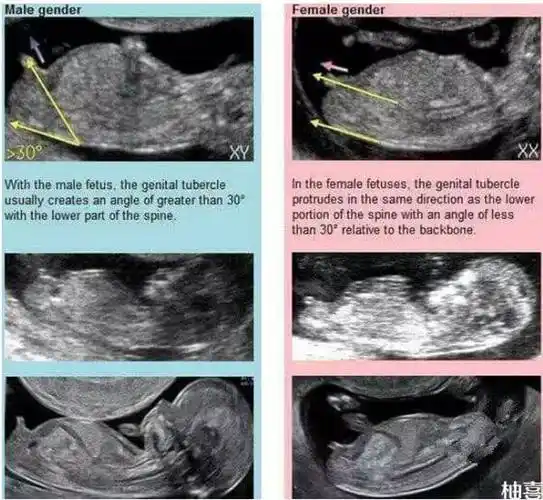

看男女,nub(nub theory)是英国开始流传起来的,nub就是胎儿的生殖节